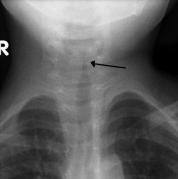

Bronchiolitis vs Croup

What is the difference between the two?

The main difference is where the inflammation occurs in the lungs.

With croup the inflammation is in the trachea, around the vocal cords.

Bronciolitis is swelling or mucus build up in the bronchioles. These are the smallest airways in the lungs.